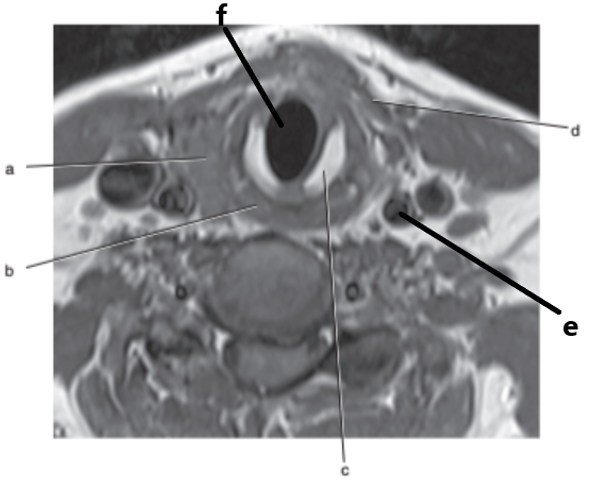

Trachea

Thyroid gland

What is letter d ?

External carotid artery

What is letter f ?

Larynx

Spinal cord

Internal jugular vein

Common carotid artery

What imaging plane is this ?

transverse

Vertebral artery

What is letter b ?

Esophagus

Cricoid cartilage